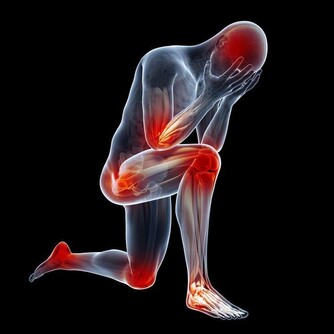

身體好不好,看膚色就知道! 這種膚色,可能是骨癌信號!

(7)皮膚發黑變粗:骨癌

這是骨癌的信號,不少胃癌患者在未發現任何症狀時,其腋下、肚臍周圍和大腿內側的皮膚會變黑變粗;有的患者面容和掌心皮膚也略呈黑色。